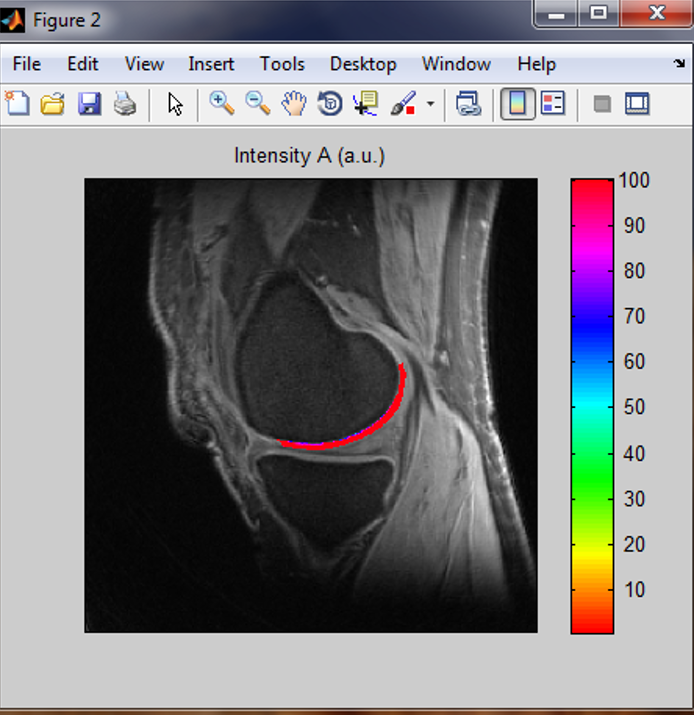

pM1 is a MATLAB-based standalone deployment which can run in a personal computer without MATLAB installed in it. pM1 is used to perform T2/T2*/T1rho mapping on MRI images in DICOM format. pM1 performs curve fitting to a model of one-term exponential decay, s(t) = A*exp(-t/T2) + n(t), on a pixel-by-pixel basis in a region of interest (ROI). It produces three maps: T2 (T2* or T1rho) map, intensity A map, and R-square (R2) map. pM1 also calculates the mean and standard deviation (SD) of T2 (T2* or T1rho) in a user-defined ROI. This software package includes a user manual which details how to install and run pM1 on your computer. pM1 has no function for motion correction.

Uploading your DICOM images is required. Curve fitting to a single-component model: s(t) = A*exp(-t/T2) + n(t). Produce three maps: T2, A, and R-square (R2). Calculate the mean and standard deviation of T2 in a user-defined ROI. To define ROI, a separate software will be provided to you for free. An example of pM1 mapping is shown in Fiure 1 above.

a

b

Figure 2. pM2 bi-component T2* mapping. (a) ROI, long-component T2* time and intensity fraction, (b) short-component T2* time, intensity fraction, and single-component-fitted T2* time.